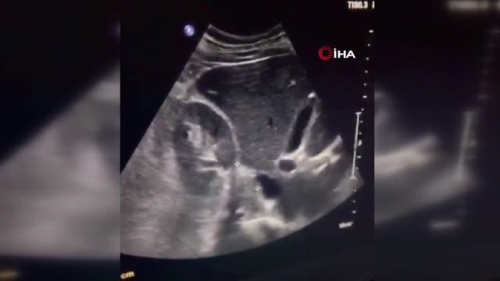

Samsun'da 37 yaşındaki Adem Günaydın, sürekli baş ağrısı, sinir, tansiyon ve insülin değerlerinin aynı düzeyde olmaması şikayetiyle gittiği her hastanede 'tip-1' diyabet tanısı koyuldu. Akabinde kullandığı haplara rağmen şikayetleri daha da artan Günaydın, şifayı tümör tanısı koyan Genel Cerrahi Uzmanı Dr. Öğr. Üyesi Kerim Güzel'in yaptığı ameliyatta buldu. Samsun'da yaşayan Adem Günaydın, şeker hastalığı, tansiyon, ve baş ağrısı şikayetlerinin artması sonucunda hastaneleri dolaşarak çare aramaya başladı. Gittiği hastanelerde tip-1 diyabet tanısı alan Adem Günaydın bu süreçte bir sürü ilaç kullandı. Akabinde Medicana International Samsun Hastanesinde görevli Genel Cerrahi Uzmanı Dr. Öğr. Üyesi Kerim Güzel'e giderek derdini anlatan Günaydın, asıl hastalığının feokromositoma(böbrek üstü tümörü) olduğunu öğrendi. Dr. Kerim Güzel ilk olarak hasta Günaydın'ı, feokromositoma düşüncesi ile endokrinoloji uzmanına yönlendirdi. Burada yapılan tetkikleri sonucunda hastanın sağ böbrek üstü bezinde 5 santimlik bir tümör kitlesi olduğu ortaya çıktı. Yapılan cerrahi işlem ile Adem Günaydın sağlığına kavuştu. Tedavi süreci Hastanın tedavi sürecinde bahseden Dr. Kerim Güzel, "Adem Bey bize şeker rahatsızlığı, diğer taraftan tansiyon yüzünde kızarma nedeniyle geldi. Dışarıda bir sürü tetikler yapılmıştı. Bu tetiklerde aslından karaciğer altında bir kitle diye geldi. Biz hastayı dinlediğimizde genç olması, tansiyon atağının olması, şekerin birden ortaya çıkmasından dolayı acaba feokromositoma, düşüncesi ile endokrine yönlendirdik. Buradaki tetikler sonucunda feokromositoma olduğu tespit edildi ve ondan sonra tedavi kolaylaştı. Önemli olan burada tanı koyulmasıydı. Bize geldiğinde birçok hastane gezmişti. Elinde bir sürü tetikler vardı ve her şeyden önemlisi bir sürü ilaç kullanıyordu. Dinleyip tanımızı koyduktan sonra endokrinoloji uzmanına yönlendirerek tanısı kesinleştirdik ve ameliyata karar verdik" dedi.